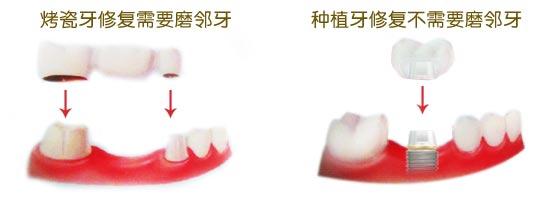

烤瓷牙,在安装烤瓷牙时,如果只是缺了一颗牙,那么牙医会做一颗烤瓷牙,然后在这个烤瓷牙的两边再做两个牙套。在安装的时候,是通过牙套套在邻近的两颗牙齿上,以达到固定假牙的目的。

种植牙,则是把一个金属制成的牙根,植入到牙床,然后再通过它来固定牙齿。这是个种植牙与烤瓷牙区别,烤瓷牙缺一补三,种植牙缺一补一。

种植牙与烤瓷牙区别,在使用效果方面来看,也是有所不同的。烤瓷牙的颜色非常的逼真,与真牙几乎没有什么区别。不过,由于安装牙套时,要磨两侧的牙齿,可能会对后来的咀嚼硬物有一些影响。而种植牙则几乎可以完全取代真的牙齿,咀嚼功能更强。